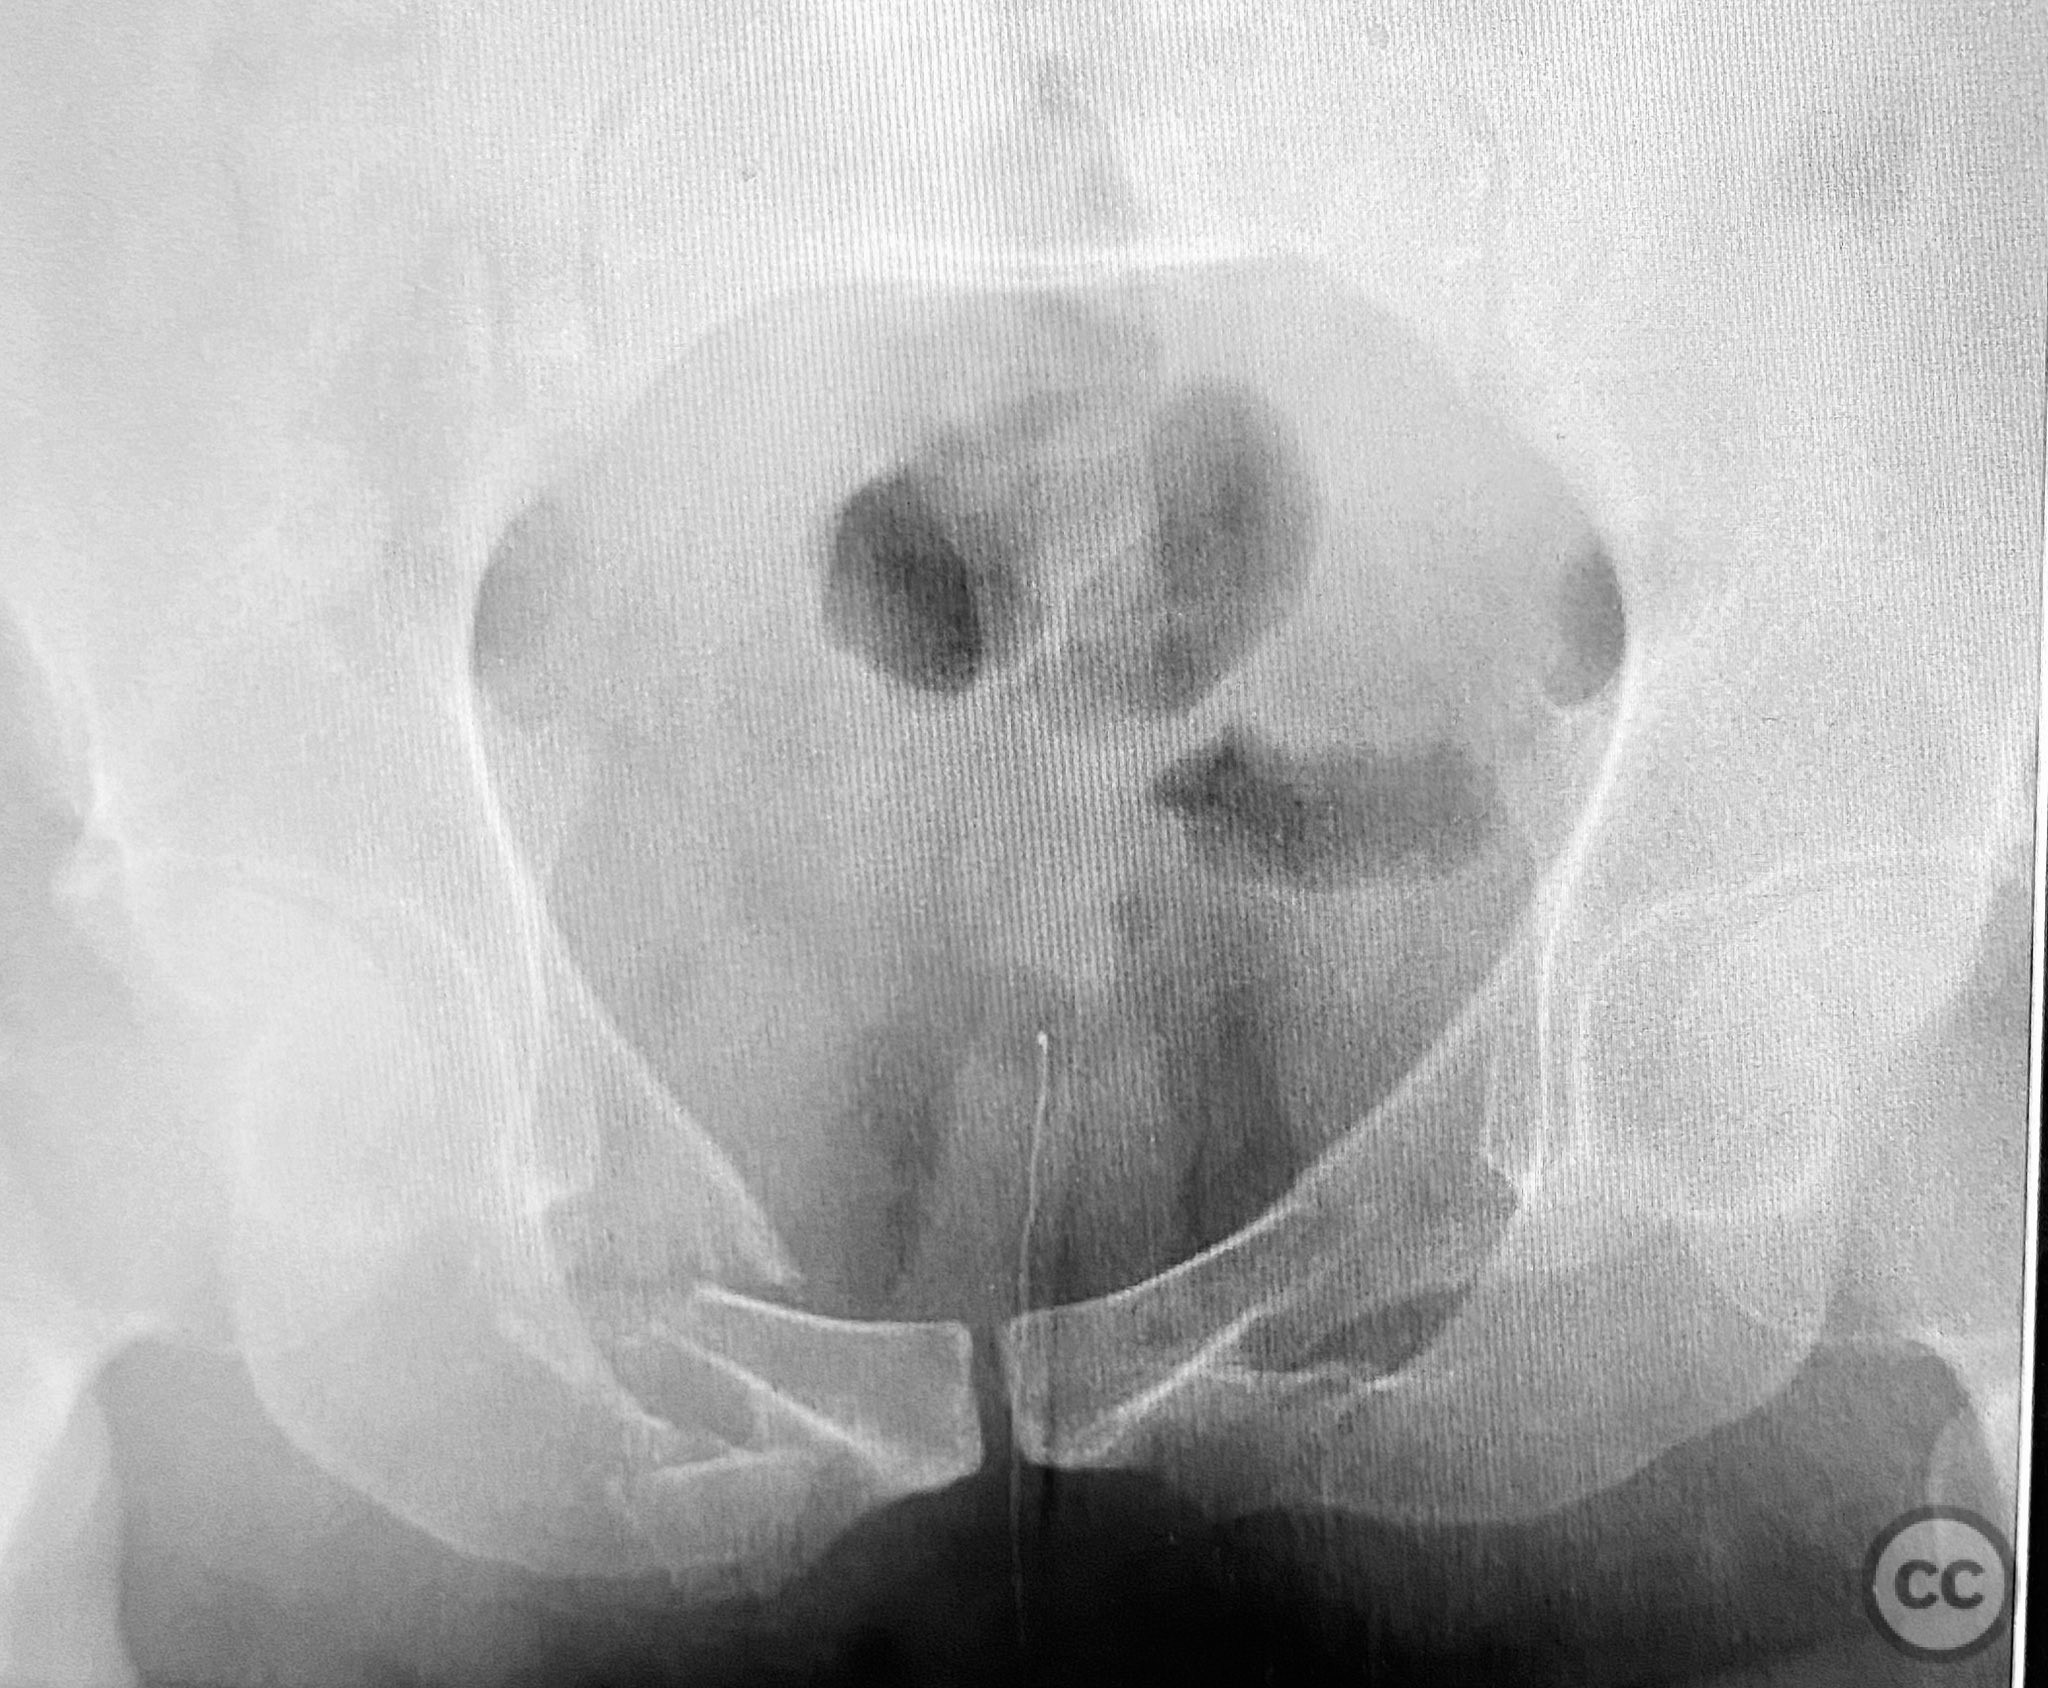

Clinical and radiological findings:  A patient presented with pelvic ring instability and deformity secondary to a left sacral fracture and a right pubic ramus fracture. Imaging demonstrated a displaced left sacral fracture (AO/OTA 61-C1.3) and a right superior pubic ramus fracture, with associated pelvic ring deformity. No neurovascular compromise was noted on initial assessment.

Planning remarks:  The preoperative plan was for closed manipulative reduction of the pelvic ring under fluoroscopic guidance, followed by percutaneous fixation of the right pubic ramus fracture and stabilization of the pelvic ring deformity using a CurvaFix intramedullary device. No open approaches were planned.

Patient positioning:  The patient was positioned supine on a radiolucent table to facilitate intraoperative fluoroscopic imaging of the pelvis in multiple planes.

Postoperative protocol:   Postoperatively, the patient was maintained toe-touch weight bearing on the affected side for 6 weeks, with progressive advancement to full weight bearing as tolerated thereafter. Early mobilization with physiotherapy was initiated to preserve hip and knee range of motion.